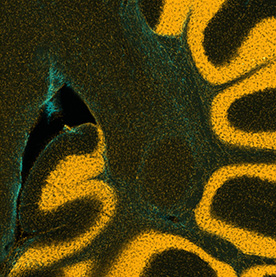

Individuals with autism experience and interact with the world differently than those without autism. Researchers use imaging methods to explore structural brain differences in humans with autism and in animal models to help identify signatures of the condition. Identifying such signatures may allow the development of improved diagnostics and treatments for autism patients.

This triptych shows three views of the folds of a mouse cerebellum, a part of the brain that helps control fine motion. In this form of artwork, the three panels create a story by highlighting a central figure with supporting imagery to either side. This triptych highlights the use of different stains for different features: yellow for the DNA inside brain cells, blue for support cells surrounding neurons. By layering multiple stains, researchers can understand how those elements interact in living tissues.